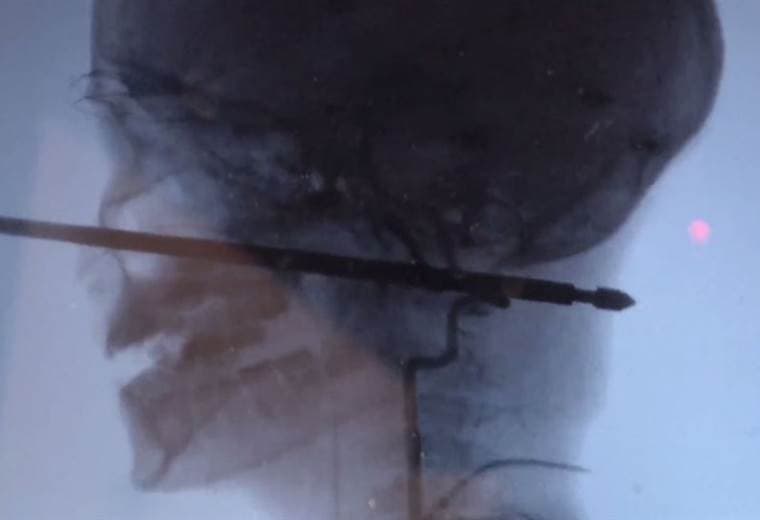

El niño que sobrevivió a un pincho para asar carne que le atravesó la cabeza

La delgada vara metálica atravesó la cabeza de Xavier "milagrosamente" evitando sus ojos, cerebro, médula espinal y vasos sanguíneos importantes.

Cuando cayó, se fue directamente contra el pincho metálico de 30 centímetros de longitud. La vara se insertó unos 15 centímetros en el cráneo.